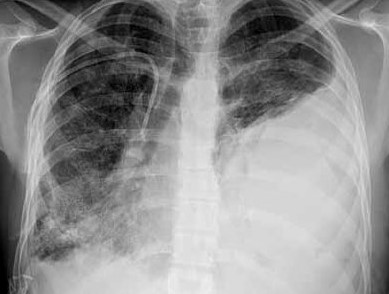

这是正常的X-光胸片

血胸或气胸大多是在 X 光胸片或胸部 CT 检查中发现。X-光检查:中量血胸X线检查可见积血上缘达肩胛角平面或膈顶上5厘米;大量血胸X线检查可见胸腔积液超过肺门平面甚至全血胸。气胸(pneumothorax)是指气体进入胸膜腔,造成积气状态,称为气胸。 多因肺部疾病或外力影响使肺组织和脏层胸膜破裂,或靠近肺表面的细微气肿泡破裂,肺和支气管内空气逸入胸膜腔。气胸,指胸腔内仅含气体,血胸指胸腔内血液积存,血气胸为二者并存。

这是血胸的X-光胸片